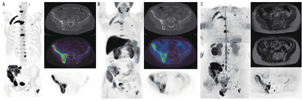

显像剂在骨内的区域性浓聚与局部血流情况和矿化活性有关,氟离子取代羟基磷灰石晶体中的氢氧根离子,从而在骨矿物质中形成氟磷灰石。通过肾脏排泄快速清除软组织本底的放射性,18F-fluoride几乎近100%首次通过骨摄取,在注射后1 h即可获得骨-本底良好对比度(图2A)[15]。

2.18F-胆碱和11C-胆碱PET/CT。18F-FDG在激素敏感性前列腺癌中往往显示低摄取,而在去势抵抗性前列腺癌中却有着较高程度的18F-FDG摄取,18F-FDG可用于监测全身治疗反应[47]。为了更准确分期,研究者对高摄取可替代显像剂的应用更感兴趣。前列腺癌与胆碱转运体、胆碱激酶表达上调以及胆碱整合进入增殖肿瘤的细胞膜有关。11C和18F标记的胆碱均可用于高风险前列腺癌的分期诊断和生化复发评价(图2B)。活动性成骨性骨转移灶的胆碱活跃程度较正常骨髓组织高,而且少见的溶骨性的转移灶也表现出更高的摄取[48]。与骨显像相比,胆碱PET/CT在高风险患者分期[49,50]及生化复发的评价上有更高的准确性[51]。